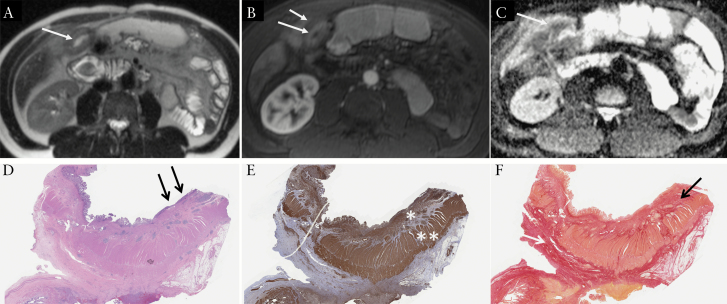

Figure 2.

A 45-yearold male patient with ileal Crohn’s disease who underwent small bowel resection for bowel stricture. MRI demonstrates: A] thickened ileal wall [at 10.5 mm] on T2-weighted image [arrows]; B] layered pattern of enhancement [enhancement of the mucosa only [long arrow], with submucosal oedema [short arrow]] on early post-contrast T1-weighted image; C] corresponding low ADC [at 1.06 × 10-3 mm2/s] on the ADC map, which suggests the presence of inflammation; [D] on histopathology, the affected ileum shows mucosal ulcerations [black arrows] and prominent mural thickening in the bowel wall [x 2 H&E]; [E] smooth muscle actin immunostain [SMA] highlights muscle layers in the bowel wall, and there is marked expansion and increase in smooth muscle [coloured in brown] within the muscularis mucosae [*] and muscularis propria [**] layers; [F] Sirius red stain highlights collagen in red, which is predominantly in the submucosa [black arrow] and subserosa [white arrow]. The ratio between normalised SMA and normalized Sirius red was 2.29 [prominent muscle hypertrophy]. H&E, hamatoxylin and eosin.